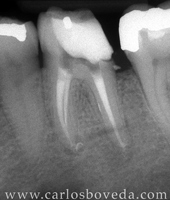

Retratamiento de Conductos en Una Sesión - (formato Quicktime)